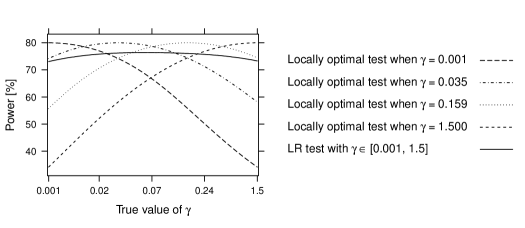

In this section, we compare the power of the LR test to tests that are optimal for specific values of : assume that the true model is an Emax model with a parameter value ; then, as discussed in Section 2.4, the t-test of versus in the linear model using the true parameter , is uniformly most powerful invariant. We will refer to this test as locally optimal for . These tests provide a useful upper bound for the performance of the likelihood-ratio test.

Consider again the dose-response trial with dose levels . We take 20 observations per dose level and choose the non-centrality parameter (Seber and Lee, 2003, Section 6) so that the locally optimal test has power for a one-sided type I error of .

For scenarios with different values from , we look at the power of a LR test with , and the power of locally optimal tests for the four parameter values . These parameter values are chosen so that the corresponding points are separated by equal distances along the model curve . The critical value of the LR test is given by . In Figure 6 it can be seen that the LR test achieves a power above 70% over the whole range of and is rather close to the respective locally optimal test. The power of the each locally optimal tests decreases markedly, when the parameter is mis-specified. For example the optimal test for has only around 50% power when the true value is .